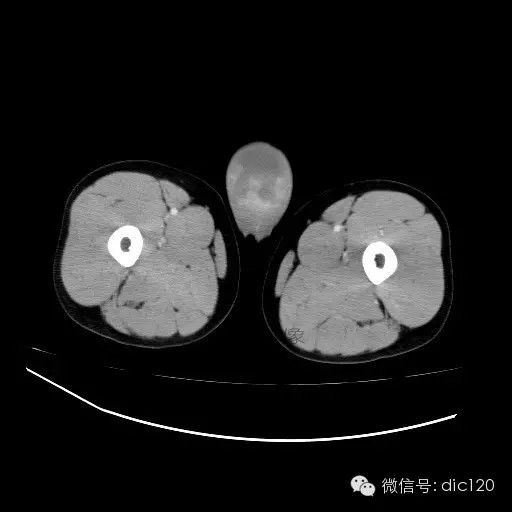

【影像表现】

青年男性,右侧睾丸肿大,边界清晰,增强后睾丸不均匀中度强化,内可见多灶囊变坏死区,动脉期肿块内有细小动脉血管显示,延迟期可见分隔样强化,鞘膜囊可见积液。

定位定性:右侧睾丸恶性肿瘤。

【影像诊断】

右侧睾丸精原细胞瘤,右侧睾丸鞘膜积液。